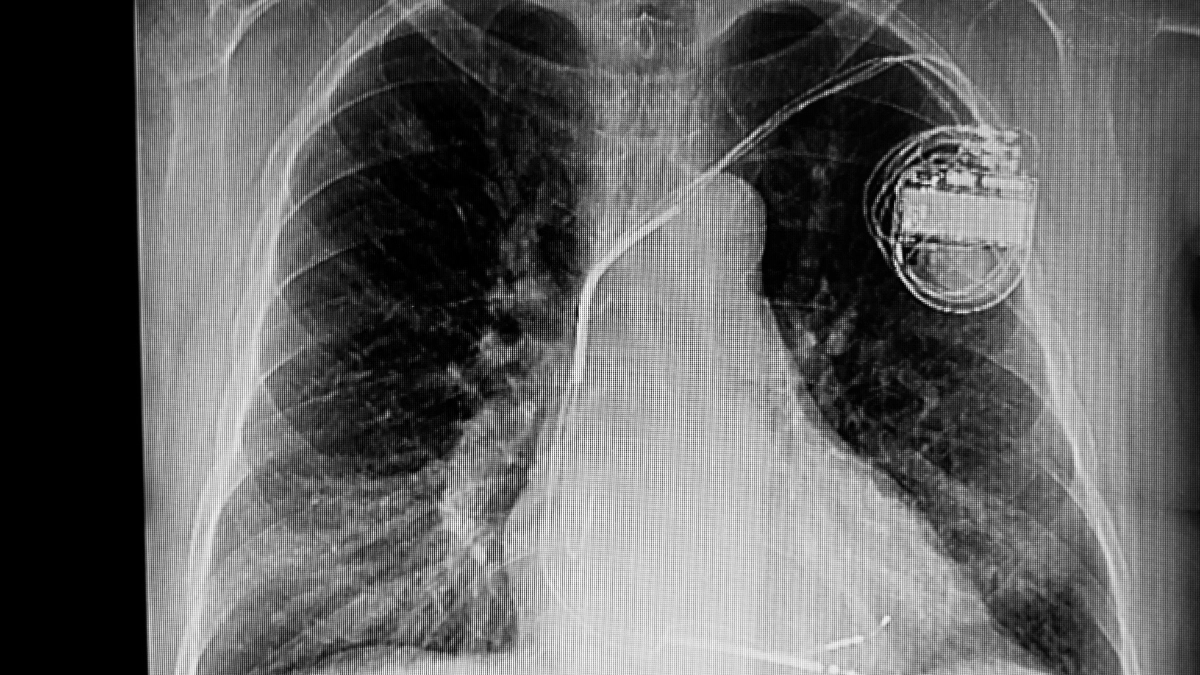

Alat pacu jantung adalah perangkat medis elektronik yang ditanamkan di dalam tubuh untuk membantu mengatur irama jantung. Alat ini bekerja dengan mengirimkan sinyal listrik kecil agar jantung tetap berdetak normal.

Prinsip kerja alat ini adalah mengirimkan impuls listrik yang menggantikan fungsi alami jantung saat terjadi gangguan. Alat ini terdiri dari dua komponen utama:

- Generator: Sebuah unit kecil berisi baterai dan rangkaian elektronik yang menghasilkan sinyal listrik.

- Elektroda (leads): Kabel tipis yang menyalurkan sinyal dari generator ke jantung.